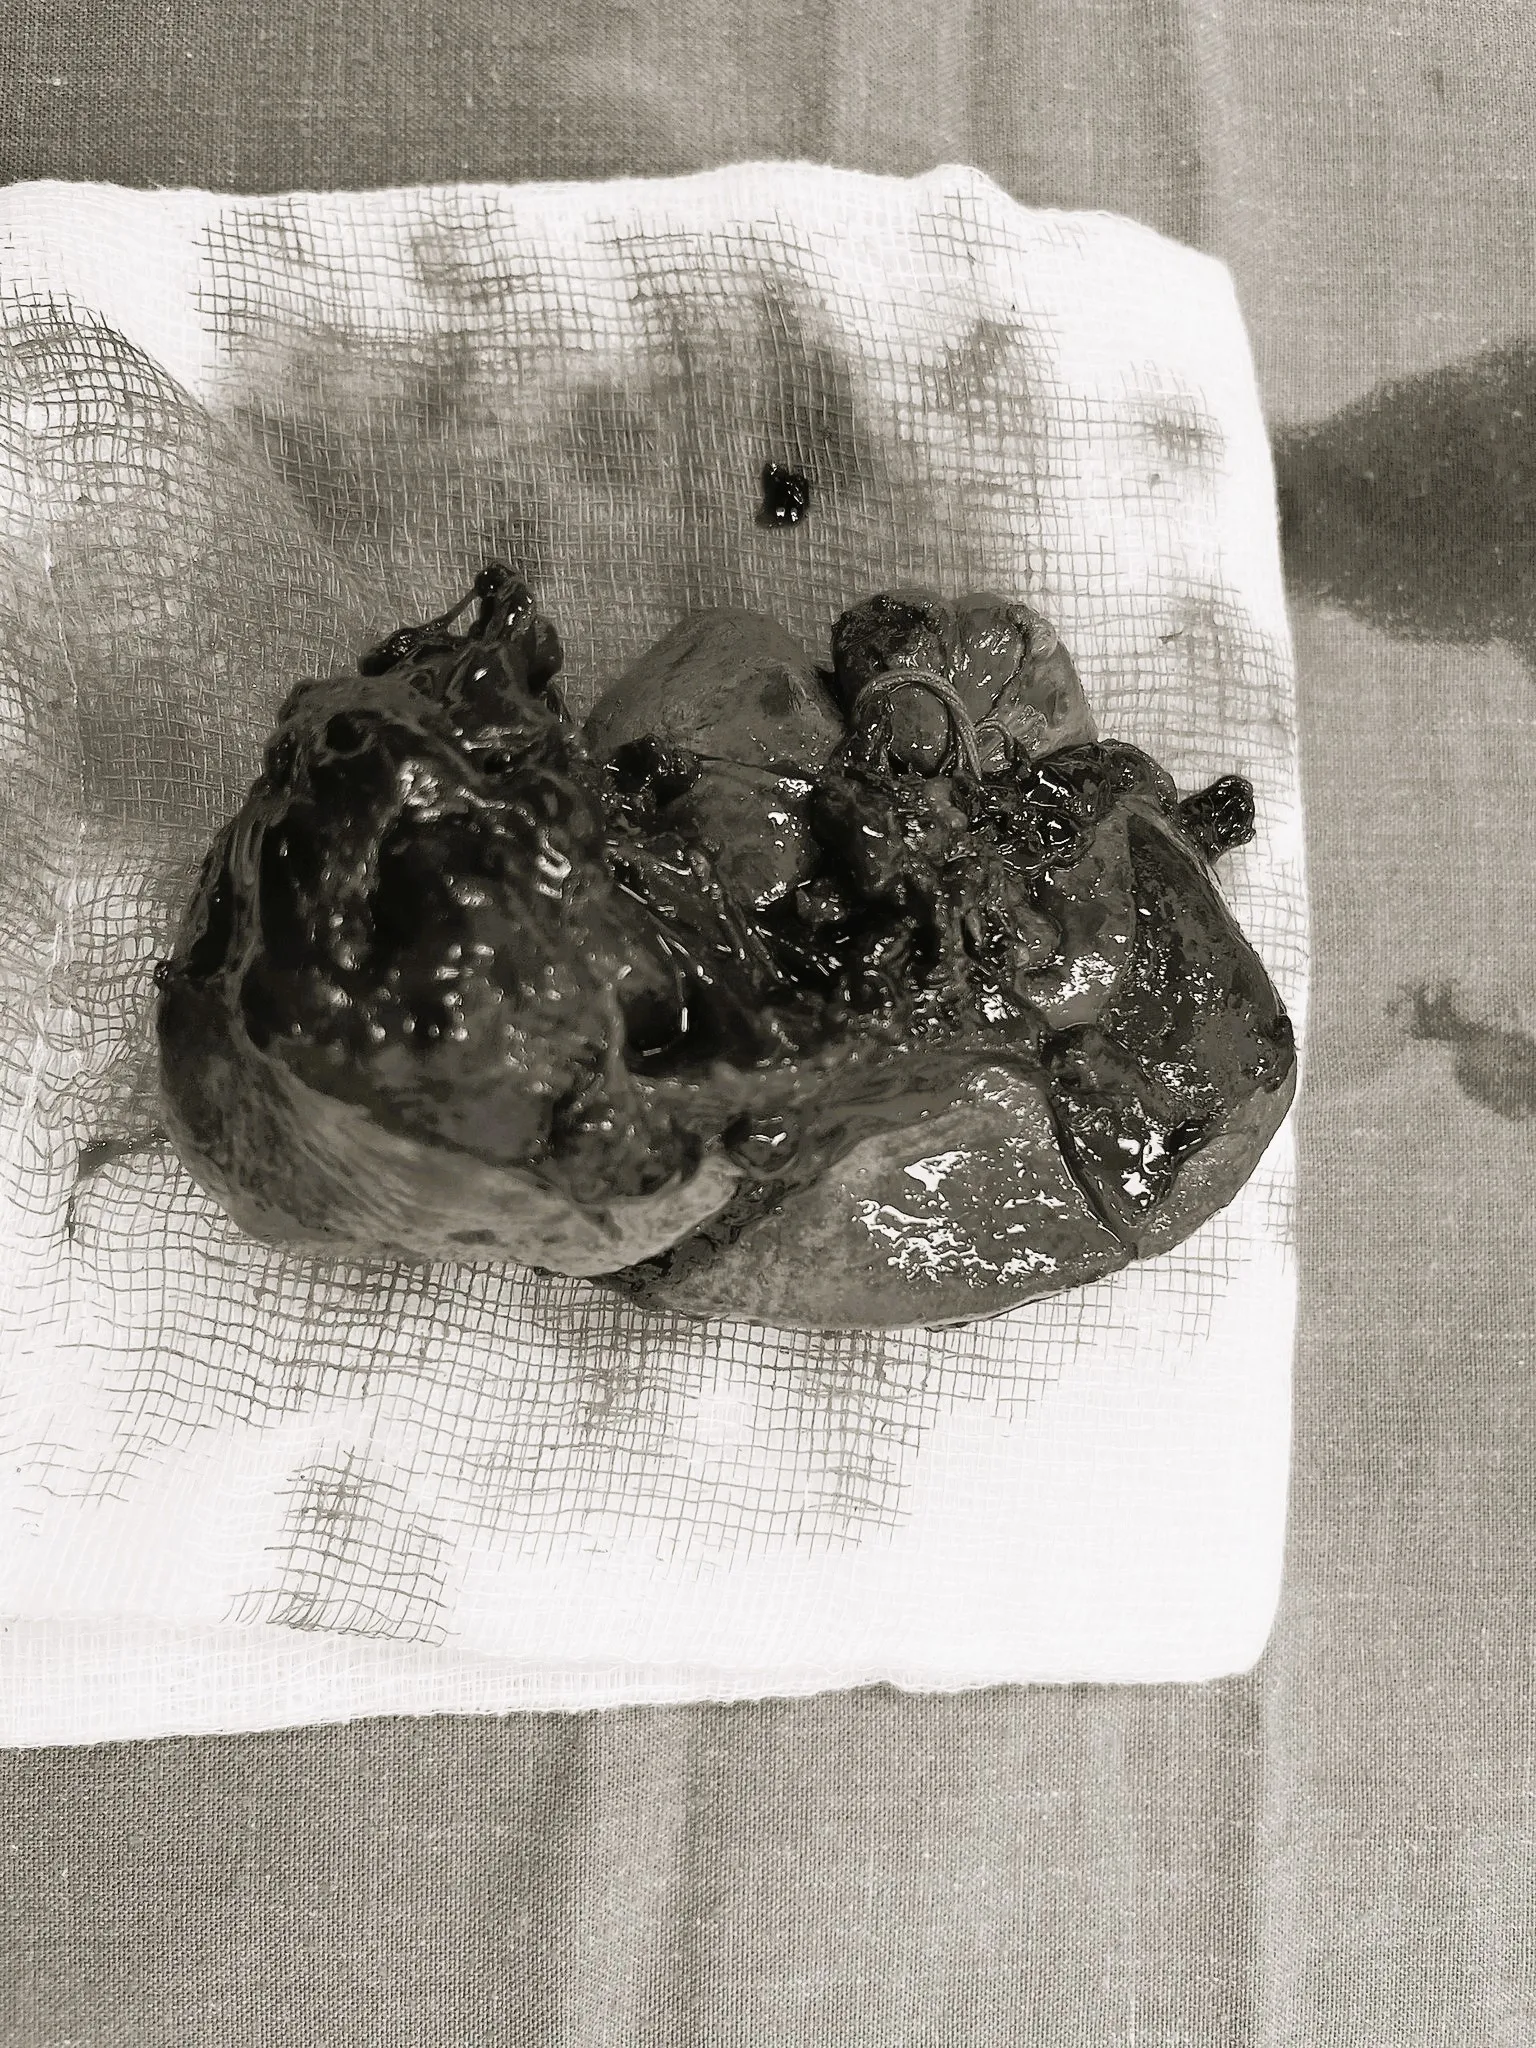

Qua thăm khám lâm sàng và cấp cứu lâm sàng cho thấy, chấn thương chảy máu nhiều trong ổ bụng do vỡ lách độ IV, gãy xương sườn 8, 9, 10, 11 bên trái, nguy cơ tử vong cao trên nền bệnh nhân đã mở cắt đoạn dạ dày cách đây 5 năm. Theo đó, các bác sĩ chuyên khoa Hồi sức cấp cứu-Ngoại khoa-Phẫu thuật gây mê-Huyết học-Truyền máu của BV Kiến An đã phối hợp, tiến hành phẫu thuật cấp cứu khẩn cấp để xử lý các tổn thương cho nguời bệnh.

Chia sẻ về ca bệnh này, bác sĩ chuyên khoa Nguyễn Hải Bình, Phó trưởng khoa Ngoại tiêu hoá, Bệnh viện Kiến An cho biết: Đây là trường hợp chấn thương ổ bụng, lồng ngực rất phức tạp do tổn thương đụng đập vỡ lách, số lượng máu trong khoang ổ bụng tới 1.200ml. Bệnh nhân có thể tử vong ngay lập tức do sốc mất máu. Vì vậy việc phẫu thuật phải được thực hiện khẩn trương mới có hi vọng cứu sống bệnh nhân.